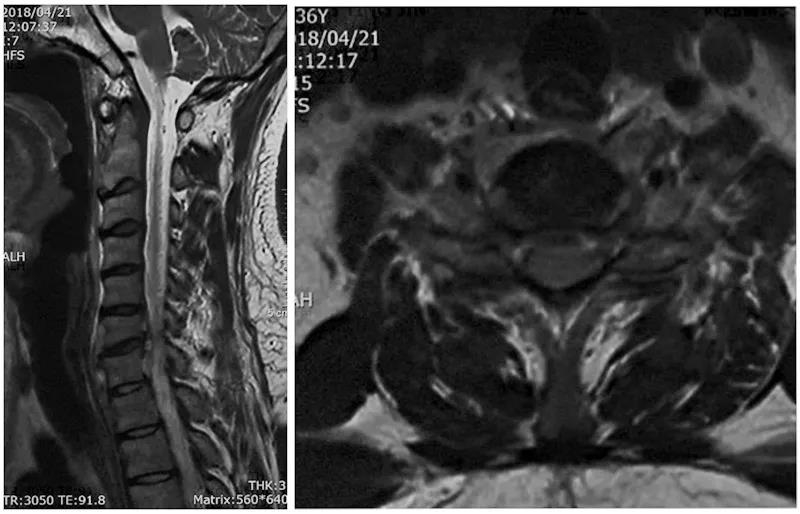

术前X线

术前CT

术前核磁

术后X线正侧位片